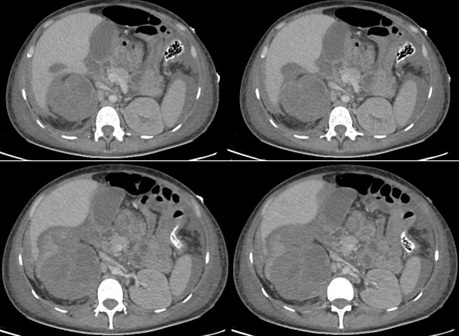

Paciente de 27 años, sexo femenino con antecedentes patológicos de artritis, síndrome de Raynoud, cistitis xantogranulomatosa, glucosuria familiar, anemia ferropénica asociado a cistitis hemorrágica, infecciones urinarias a repetición en los últimos 2 años (4 episodios por año) y hospitalización reciente por candidiuria, tratada previamente. Cursó con cuadro clínico de fiebre no cuantificada, disuria, polaquiuria, reporte de urocultivo ambulatorio con presencia de Klebsiella pneumoniae multisensible, es tratada con control de urocultivo negativo. Laboratorios de seguimiento con hemograma: leucocitos 12.30 ul, hemoglobina 10.60 g/dl, hematocrito 34.50%, plaquetas 297000 mcL, neutrófilos 9.95 ul, linfocitos 1.37 ul, monocitos 0.6ul. Uroanálisis: color rojo, aspecto turbio, PH 6.5, nitritos negativos, glucosa >1000 mg/dl, leucocitos 25-30 xc, hematíes 30-55 xc, células epiteliales 0-2 xc, bacterias escasas. Función renal: BUN 9.50 mg/dl, creatinina 0.81mg/dl. Otros resultados: potasio 4.50 mmol/L, albumina 3.33 g/dl, hierro total 13.00 ug/dl, ferritina 1826.67 ng/ml, proteinuria en 24 horas 618.75 mg/24 horas, proteinuria en orina ocasional 137.5 mg/L, volumen de orina de 24 horas: 4500 ml/24 horas. Durante su seguimiento por nefrología se encontró cuadro clínico de 15 días de evolución caracterizado por persistencia de síntomas urinarios irritativos acompañado de leve distensión abdominal y dolor en hemiabdomen derecho por lo cual ingreso al servicio de urgencias, iniciando manejo farmacológico, vigilancia hemodinámica y control radiológico con ecografía renal con presencia de engrosamiento urotelial, alteración en la ecogenicidad del parénquima del riñón derecho por pielonefritis y/o cambios de nefropatía, además de engrosamiento de las paredes vesicales en relación con cambios inflamatorios, presencia de gas intraluminal, restos hemáticos o detritus en la luz vesical e imágenes que pueden corresponder a restos hemáticos impactados o pólipos. Durante su estancia hospitalaria se observó reactantes de fase aguda en aumento, conservación de la función renal, hemograma con leucocitosis y neutrófilia, anemia moderada hipocromica microcitica, por lo cual se escalonó esquema de antibioticoterapia. Además, se realizaron cultivos de orina de forma seriada encontrando bacilos de Mycobacterium tuberculosis en la cuarta muestra analizada. En su día 5 de hospitalización presento choque hemodinámico, anemización severa aguda, insuficiencia respiratoria severa con requerimiento de hospitalización en unidad de cuidados intensivos (UCI), soporte ventilatorio, vasopresor y transfusión de hemoderivados. Por el deterioro clínico se realizó tomografía computarizada de abdomen y pelvis con impresión diagnostica de laceración del polo superior del riñón derecho con hematoma en el espacio pararrenal anterior, sangrado activo, contusión hepática en el segmento VI, también presencia de cambios de pielonefritis xantogranulomatosa derecha, dilatación ureteral a nivel de la pelvis renal, uréter derecho y engrosamiento vesical (Figura 1 y Figura 2).

Riñón derecho con pérdida de la estructura corticomedular, contenido hipodenso de hematoma intrarrenal contenido en la Gerota y disrupción del parénquima en el polo superior.

Figura 1 Tomografía computarizada de abdomen y pelvis